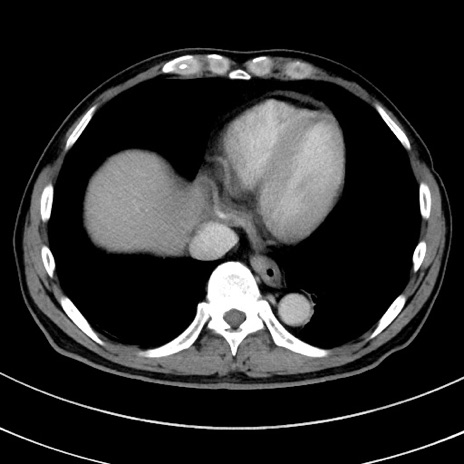

症例8(横断像)

【症例】 60歳代男性

【主訴】 黒色吐物

【現病歴】 4日前から嘔気自覚、2日前の朝食後にも嘔気あり、自分で手で嘔吐反射起こし嘔吐したところ血が混ざっていたため受診。

【既往歴】 5年前汎発性腹膜炎を伴う急性虫垂炎で手術、高血圧、前立腺肥大症、高脂血症

【身体所見】 腹部正中に手術癩痕あり 腹部平坦・軟圧痛なし膨満感あり

【データ】WBC 8400、CRP 4.54